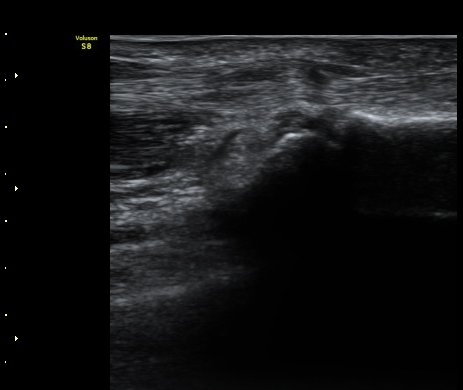

¼Õ°¡¶ô ½ÅÀü ½Ã ºÎÀº ÈûÁÙÀÌ a1ÇÒÂ÷¸¦ Åë°úÇÏÁö ¸øÇÏ°í °É¸°´Â ¸ð½ÀÀÌ °üÂûµÊ(±×¸² 4).

ÈûÁÙÀÌ °É¸®´Â ¸ð½ÀÀº µ¿¿µ»ó(÷ºÎ ÆÄÀÏ)¿¡¼­ ¶Ñ·ÈÈ÷ °üÂûµÊ.